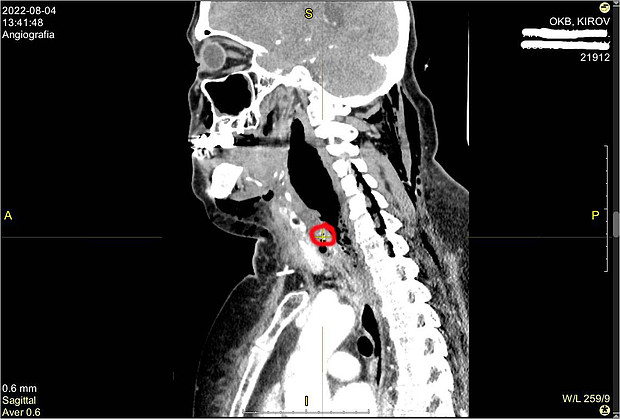

В областную клиническую больницу ее привезли в тяжёлом состоянии из-за сильнейшего обезвоживания и интоксикации. Компьютерный томограф показал врачам инородное тело в шейном отделе пищевода и флегмон шеи верхнего средостения. Из-за, что женщина медлила с визитом к медикам, гнойное воспаление тканей опустилось вниз, в полость между лёгким и сердцем. Там развился передний медиастинит. Это чрезвычайно опасное для жизни инфекционное воспаление клетчатки средостения, причиной которого стала перфорация пищевода.